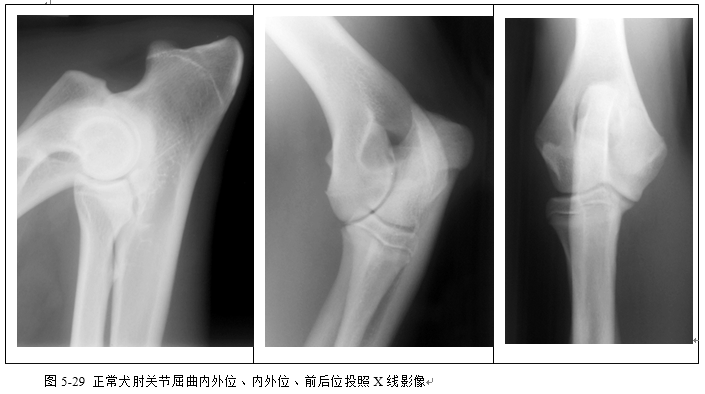

(2)识别桡尺骨、肱骨、肘关节、腕关节、肩关节X线影像(图5-28、5-29、5-30、5-31)。

二、能动关节的X线解剖

(一)关节面 X线片上表现的关节面为骨端的骨性关节面,由骨密质组成,呈一层表面光滑整齐的致密阴影。

(二)关节软骨 关节软骨正常时在X线片上不显影,关节内造影时,关节面和造影剂之间显示一条线状低密度阴影。

(三)关节间隙 由于关节软骨不显影,X线片上显示的关节间隙包括大体解剖中见到的微小间隙和关节软骨。